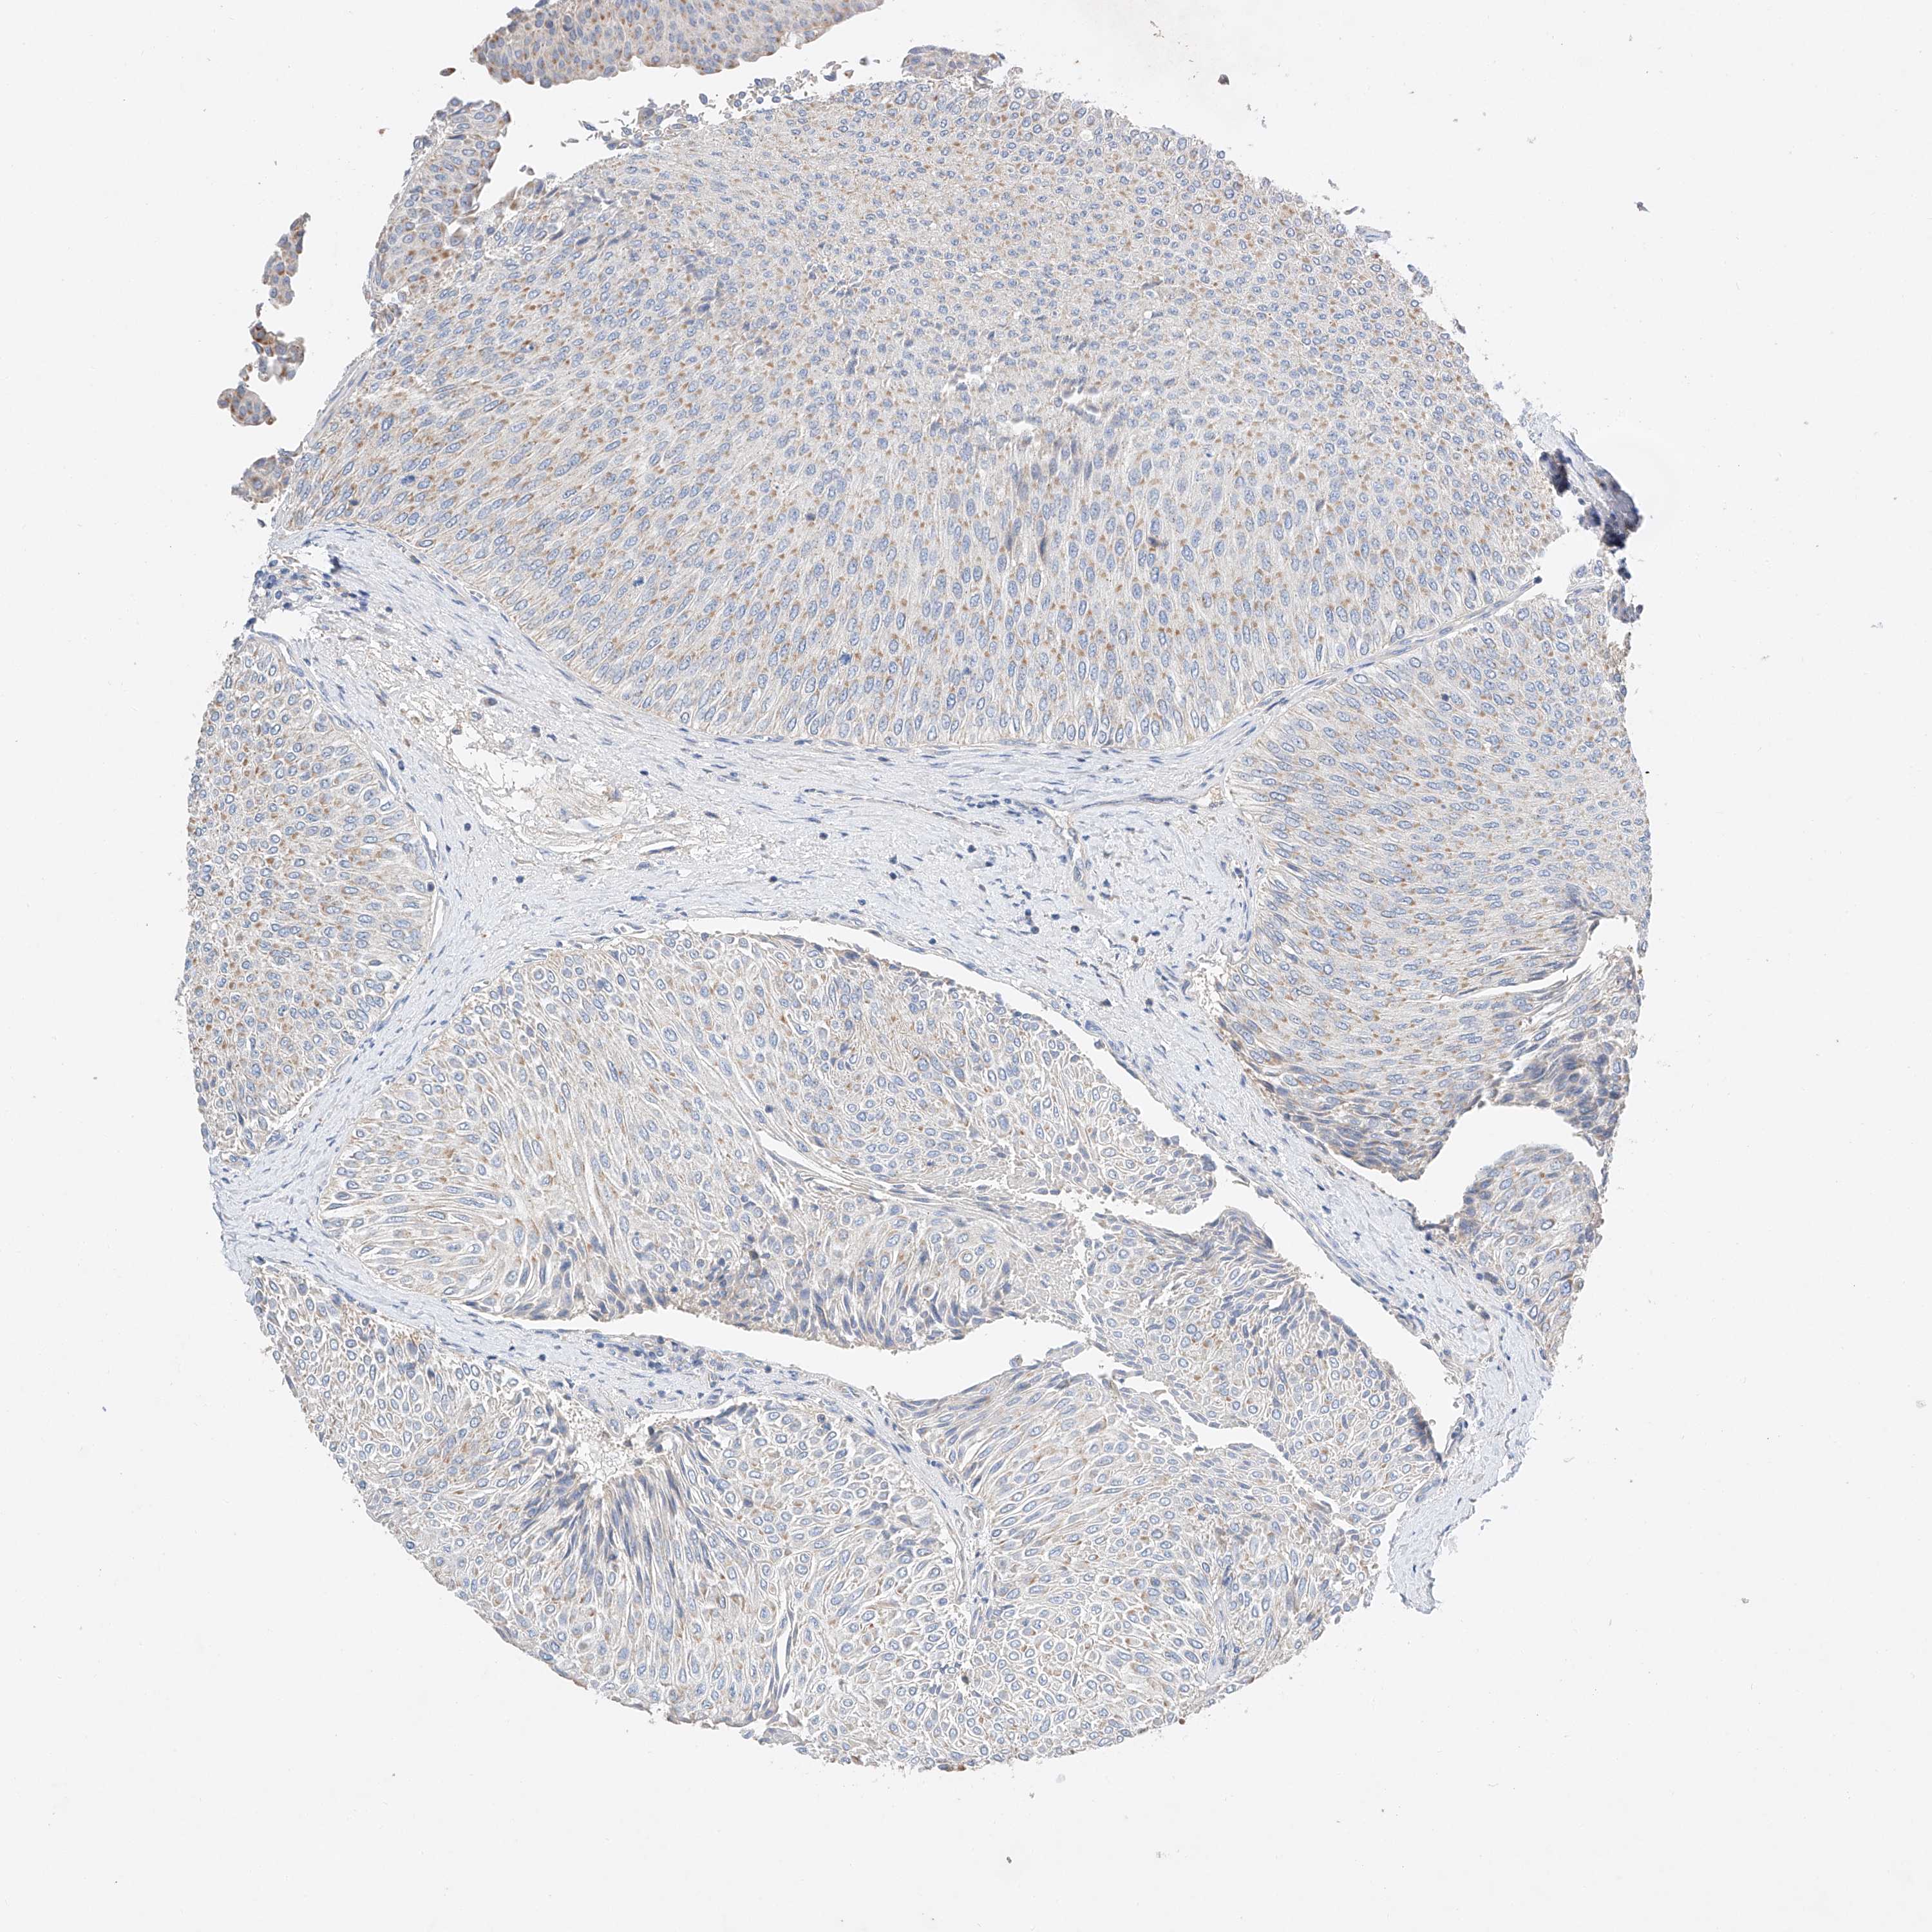

UROTHELIAL CANCER - Protein expressioni

A mouse-over function shows sample information and annotation data. Click on an image to view it in a full screen mode. Samples can be filtered based on level of antibody staining by selecting one or several of the following categories: high, medium, low and not detected. The assay and annotation is described here.

Note that samples used for immunohistochemistry by the Human Protein Atlas do not correspond to samples in the TCGA dataset.

Antibody stainingi

Antibody staining in the annotated cell types in the current human tissue is reported as not detected, low, medium, or high, based on conventional immunohistochemistry profiling in selected tissues. This score is based on the combination of the staining intensity and fraction of stained cells.

Each image is clickable and will lead to virtual microscopy that enables deeper exploration of all samples and also displays staining intensity scores, fraction scores and subcellular localization as well as patient and tissue information for each sample.

Antibody HPA030295

Antibody HPA054323

Urothelial carcinoma, Low grade

Urothelial carcinoma, High grade